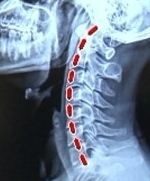

위의 사진에서 보시다시피 H컵녀와 정상인의 촬영한 화면은

눈에 띄게 다르다는 것을 느끼실수 있습니다